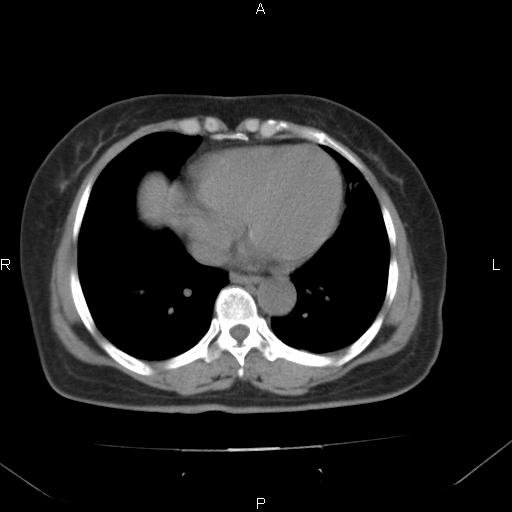

胸腺瘤

女、63Y 双眼睑下垂,早轻晚重。 胸腺瘤???

结果胸腺瘤